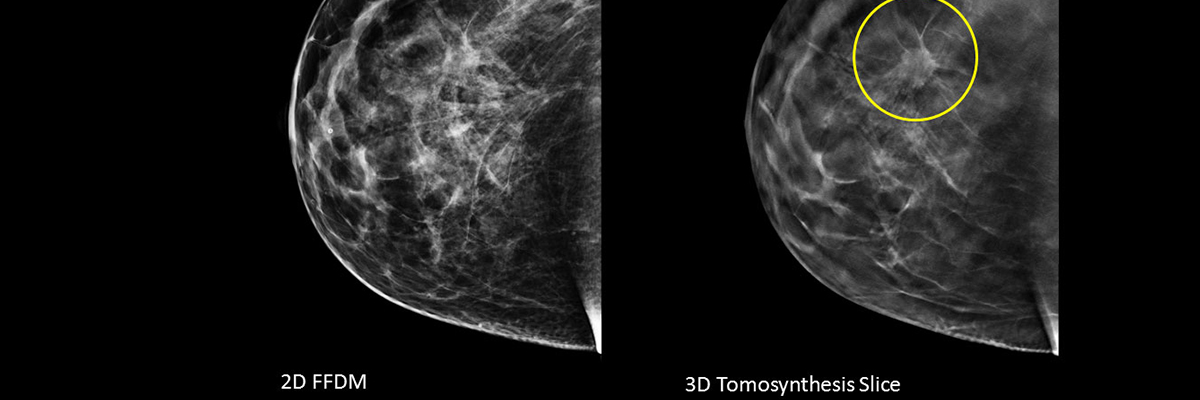

3D TOMO MAMMOGRAPHY

DRCTC is proud to have a mobile 3D TOMO MAMMOGRAPHY. This system boasts a wide variety of revolutionary advancements, including being the only Open Gantry Design 3D TOMO MAMMOGRAPHY in the marketplace. The system produces the fastest total body imaging time of any 3D TOMO MAMMOGRAPHY currently available and the multi-slice CT, allows for highly accurate and precise anatomical mapping.

scheduling

3D TOMO MAMMOGRAPHY are performed at our both location. This system boasts a wide variety of revolutionary advancements, including being the only Open Gantry Design 3D TOMO MAMMOGRAPHY in the marketplace.